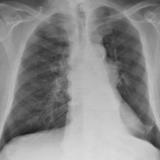

BAC

Album: BAC

Date: 09/10/2006

Size: 9 items

Views: 42606